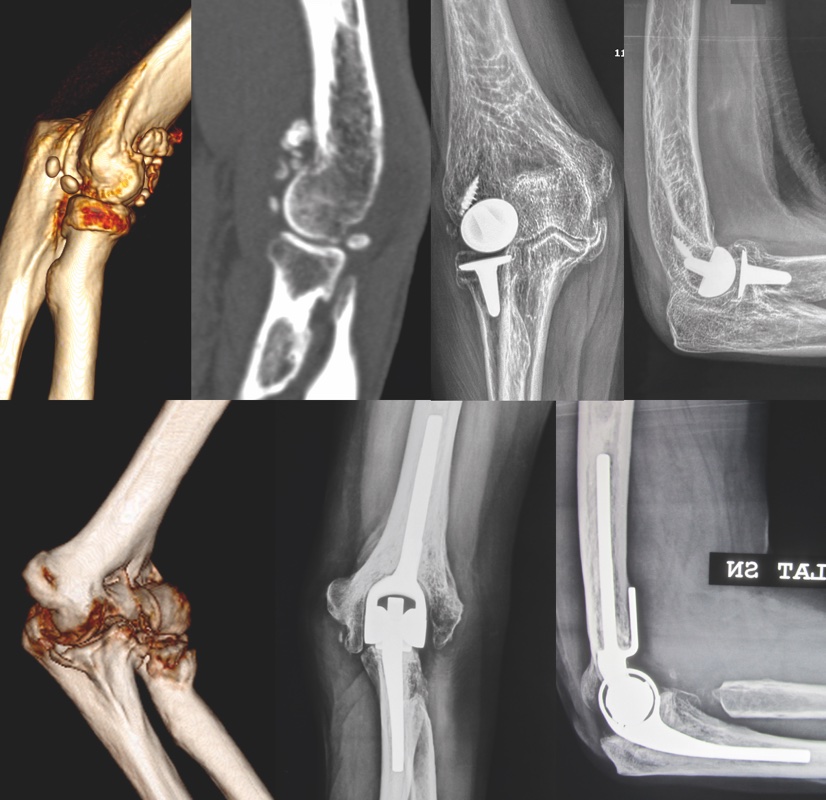

La TC del gomito con ricostruzioni 2D e 3D rappresenta un esame di secondo livello fondamentale in questa patologia, in quanto consente di ottenere una visione tridimensionale del gomito estremamente utile per inquadrare la rigidità e per programmare l’intervento chirurgico. La RM del gomito, l’ecografia statica e dinamica e l’esame EMNG completano in alcuni casi lo studio diagnostico.

Il trattamento della rigidità può essere sia di tipo chirurgico che conservativo. Il trattamento conservativo è indicato nei pazienti che hanno osservato un periodo più o meno lungo di immobilizzazione post trauma e per i quali l’insorgenza della rigidità è < 6 mesi. In tali casi, in assenza di elementi con valore prognostico negativo, quali l’incongruenza articolare e i vizi di consolidazione intra-articolari, è indicato eseguire un percorso riabilitativo con supervisione di un fisioterapista esperto. Il trattamento chirurgico della rigidità è estremamente complesso e ha carattere fortemente “personalizzato”. In caso di patologia artrosica primaria o secondaria il trattamento, valutato il grado di usura condrale, è mirato alla liberazione da processi osteofitari delle fossette olecranica e coronoidea così come all’asportazione di corpi liberi e capsula retratta. In caso di grave artrosi, è indicata la sostituzione protesica del gomito (totale o parziale) (Fig. 1).

In caso di esiti traumatici con vizi di consolidazione e/o pseudoartrosi il trattamento prevede la valutazione dello stato delle superfici articolari, dei vizi di consolidazione (intra o extraarticolari), della sede e tipologia della pseudoartrosi, della presenza di mezzi di sintesi e dello stato neurologico. In questi casi, il trattamento varia dalle artrolisi, alle osteotomie di correzione e sostituzione protesica; nelle pseudoartrosi è spesso indicata la bonifica, l’apposizione di innesti ossei autologhi e la nuova osteosintesi.

Instabilità cronica complessa persistente e ricorrente

Il trattamento chirurgico è influenzato da vari fattori (età, richieste funzionali, stato della articolazione) e deve mirare a ricostruire gli stabilizzatori ossei e legamentosi di questa articolazione 4. Nelle forme datate (oltre 6-9 mesi), dove è presente una degenerazione marcata delle superfici articolari, è indicato eseguire una protesi totale del gomito.